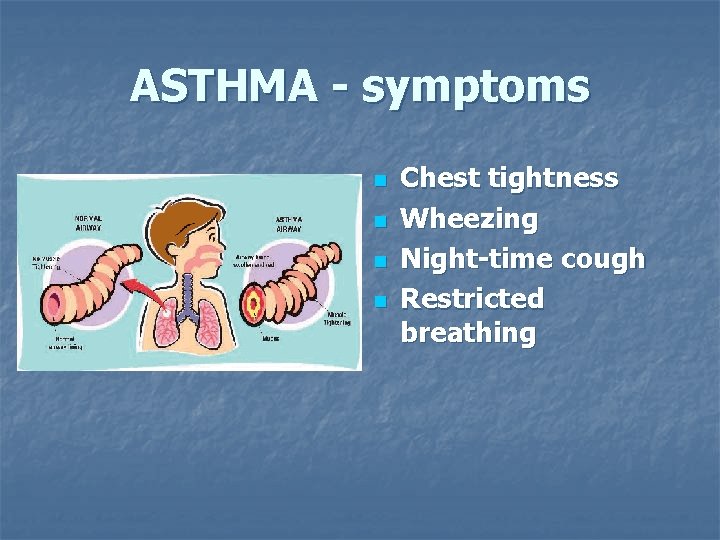

ASTHMA - symptoms n n Chest tightness Wheezing Night-time cough Restricted breathing